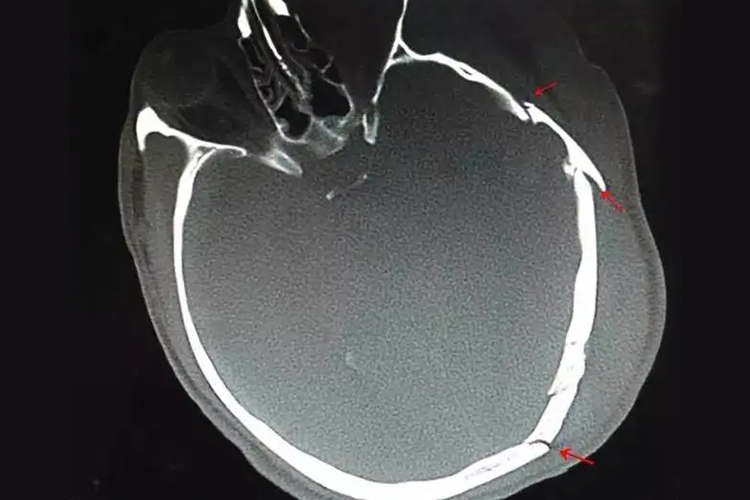

颅骨骨折CT表现可看到局部颅骨之间的连续性中断,呈现横行或纵行的骨折线。

颅骨骨折CT影像表现可以显示骨折的部位颅骨连续性中断,可见骨折线。CT在明确骨折的部位和类型的同时,还能排除是否有颅脑损伤或颅内血肿。